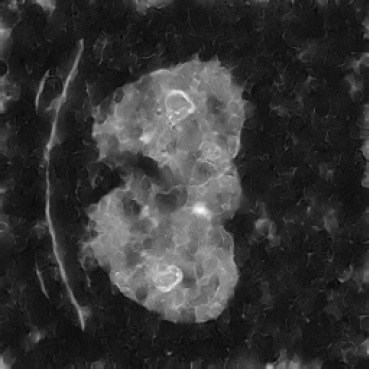

In our approach, we employ a compression factor of 4 to encode 3D medical images into the latent space. This level of compression reduces the spatial resolution of the original image (e.g., from 256×256 to 64×64 per slice), while still preserving the essential anatomical structures and semantic content. The latent representation at this scale offers a favorable trade-off between dimensionality reduction and semantic fidelity. Specifically, although fine-grained textures are simplified, key structural patterns (e.g., organ boundaries, lesion shapes) remain visually distinguishable and semantically coherent. As the compression rate increases, the latent representations become progressively more abstract. With lower compression (e.g., 2× or 4×), the latent features preserve key anatomical structures and spatial layouts, making them beneficial for our semantic image synthesis task in latent space, as the model can operate on compressed representations that retain sufficient semantic information without being overwhelmed by high-frequency noise. In contrast, higher compression rates (e.g., 8× or above) lead to a loss of fine-grained details and reduced semantic fidelity. The choice of a 4× compression thus ensures that the latent features are compact and meaningful, facilitating effective conditional generation while significantly reducing computational overhead. We therefore adopt a 4× compression as a compromise between computational efficiency and semantic preservation. The corresponding 2D slices in image space and latent space are shown in Figure 7.